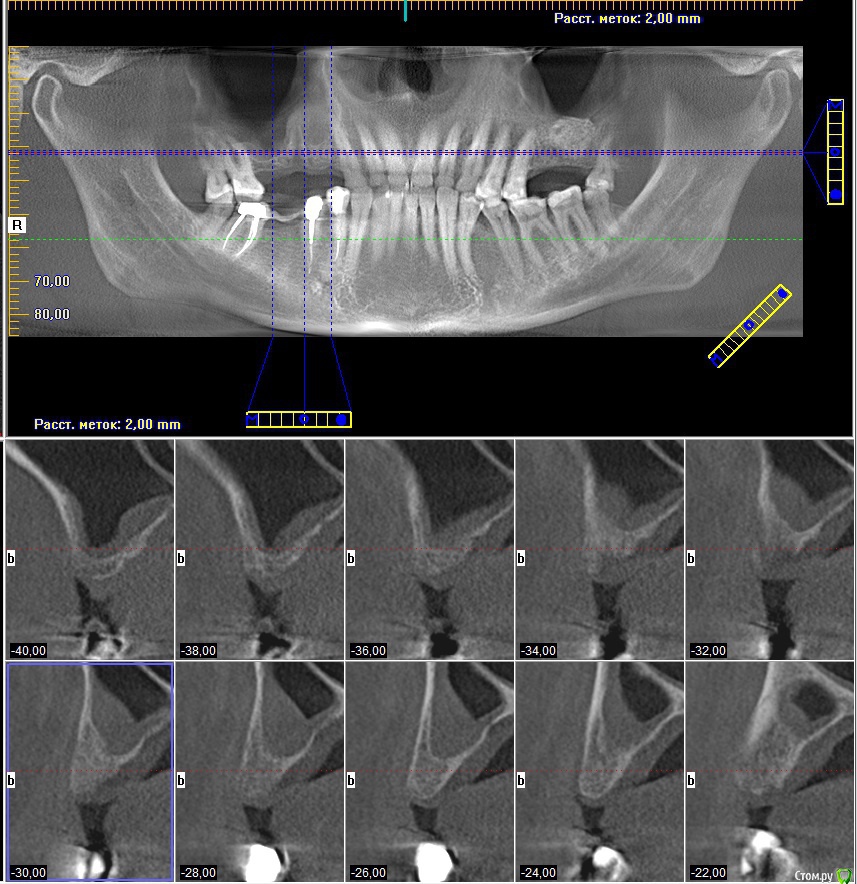

koreandr Опубликовано 23 ноября, 2018 Поделиться Опубликовано 23 ноября, 2018 Всем привет) планируется осл справа.Кт картина на срезах. Жалоб нет.Что может быть в синусе, какая тактика, подключать ли ЛОР врача? Спасибо) Ссылка на комментарий

kamranchick Опубликовано 24 ноября, 2018 Поделиться Опубликовано 24 ноября, 2018 нормально все, оперируйте в штатном режиме) Ссылка на комментарий

Bier Опубликовано 24 ноября, 2018 Поделиться Опубликовано 24 ноября, 2018 соустье надо смотреть 2 Ссылка на комментарий